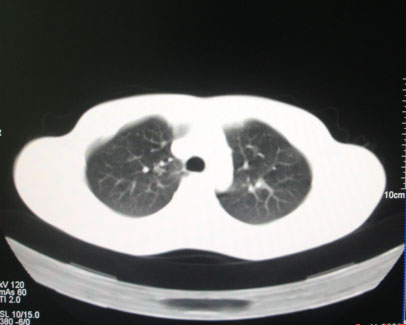

标题: CT26938:单发肺窗

病人17岁。咳嗽伴血丝痰2年?外院x片示左上肺椭圆形影,疑胸腺瘤

左肺尖见占位,建议上传纵隔窗及向上扫描。